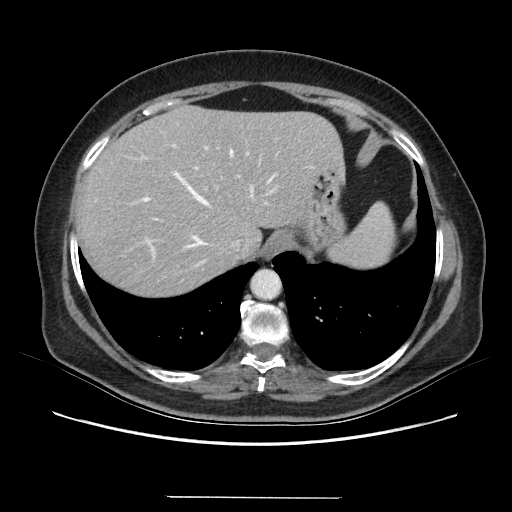

Generated VENOUS CT scan (A→B translation)

Full window (WL 1023.5, WW 4095 β†’ Low βˆ’1024, High +3071)